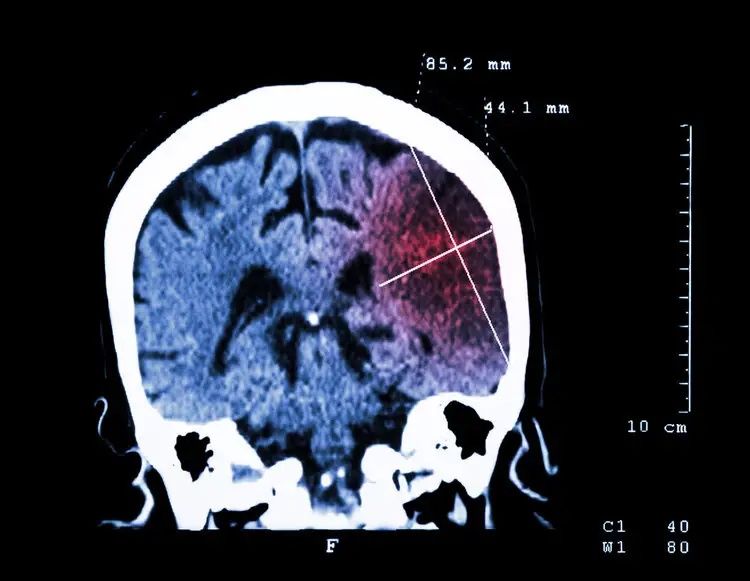

他们马上打120将王奶奶送到医院治疗,医生判断王奶奶是脑出血,马上给王奶奶做了头颅CT检查,结果显示是脑干出血。最终住院抢救24小时无效身亡。